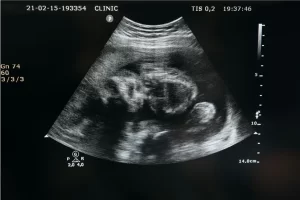

Можете да получите информация за ин витро лечение, репродуктивно здраве, гинекология, бременност и много други теми от нашите блог статии. За да получите информация за ин витро лечението, попълнете формуляра за контакт и се свържете с нас